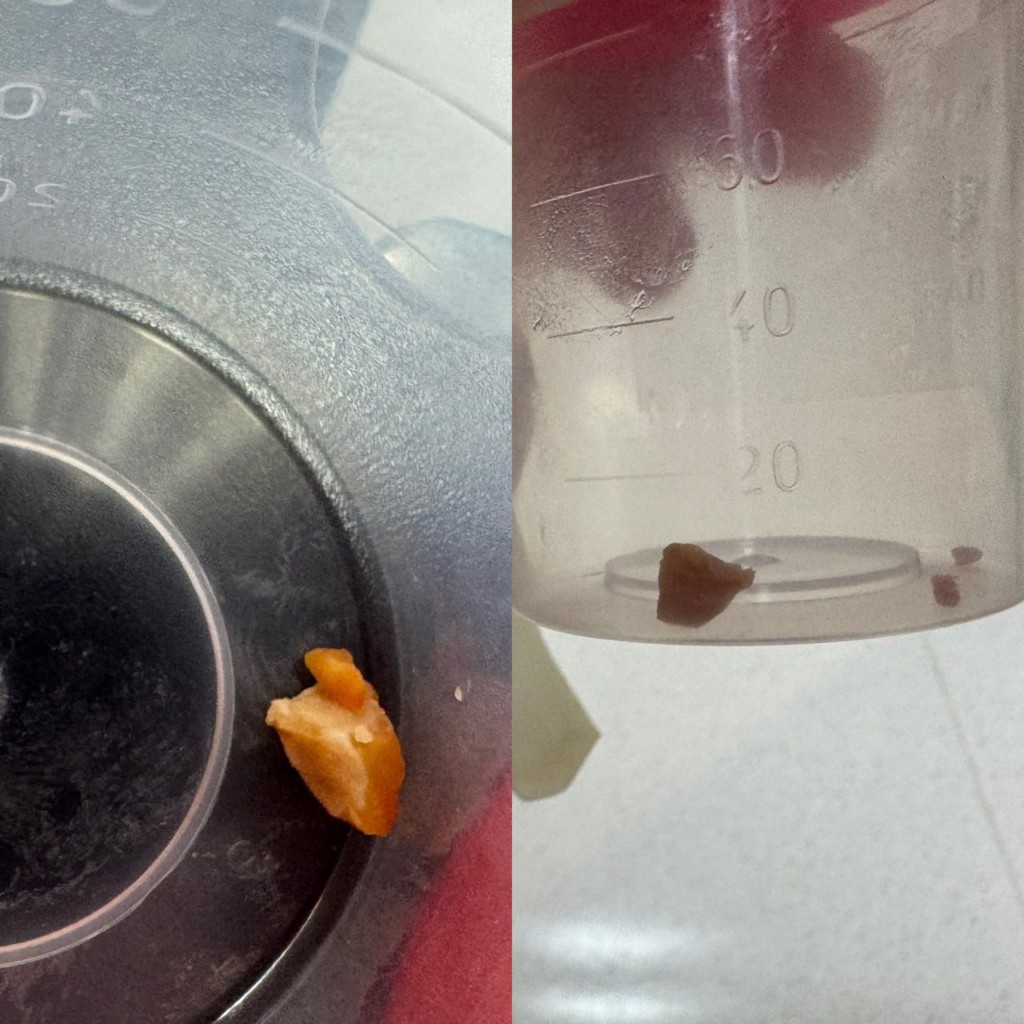

廖穗綾在貼文開頭直呼「到底為什麼還要餵小小孩吃整顆花生?」病房來了一個一歲多的孩子,3、4天前阿嬤餵了花生,之後開始咳嗽、出現喘鳴聲,剛來時症狀並不明顯,但隔天追蹤X光,竟發現肺部開始塌陷,這不是小事。

廖穗綾直言,醫師坦言,從來沒有遇過這麼困難的案例,整整將近兩個小時,在狹小氣道裡反覆嘗試,幾乎快要放棄時,那顆「會跳舞的花生」終於彈動了一下,成功網住、夾出,那刻大家都鬆了一口氣。

「但我真的很生氣!」廖穗綾坦言,這不是第一個案例,「我們到底還要講幾次?3、4歲以下,不要給整顆花生、不要給堅果,很困難嗎?」她直言,很多人會說「只吃一顆而已」、「我有在旁邊看著」、「我們以前都這樣長大」,但醫療現場看到的是,孩子咳3天才來,導致氣道發炎腫脹、肉芽生成、肺部塌陷、進開刀房、住加護病房、插氣管鏡。